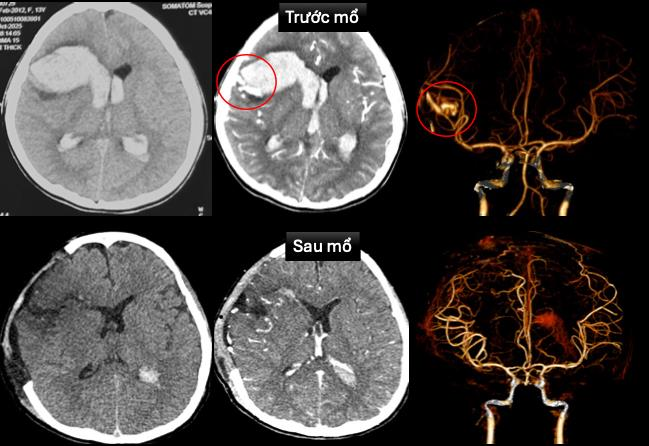

Hình ảnh chụp cắt lớp vi tính sọ não và dựng hình mạch máu não trước và sau mổ - Ảnh BVCC

Tại khoa cấp cứu, bệnh nhân được ghi nhận tình trạng hôn mê sâu, thở máy qua nội khí quản, nhịp chậm, huyết áp thấp đang duy trì thuốc vận mạch. Bệnh nhân được siêu âm tim, chụp cắt lớp vi tính sọ não dựng hình mạch máu não cấp cứu.

Bệnh nhi được chẩn đoán dị dạng động tĩnh mạch trán phải vỡ gây xuất huyết nhu mô não lan vào hệ thống não thất, sốc tim, rối loạn nhịp, bệnh cơ tim xốp.

Hình ảnh chụp cắt lớp vi tính sọ não sau mổ không còn ghi nhận dị dạng mạch máu não. Siêu âm tim kiểm tra: ghi nhận bệnh cơ tim xốp với tình trạng chức năng co bóp cơ tim cải thiện (EF 65%).